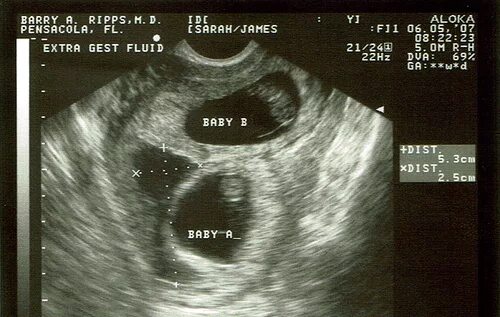

8 недель беременности вторая беременность